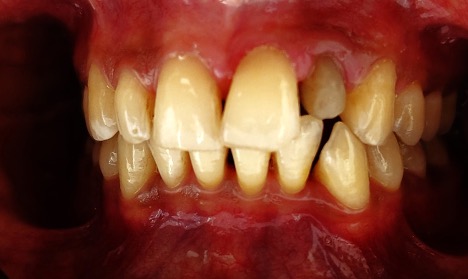

A dental crown is a tooth- shaped cap placed over a damaged or decayed tooth to restore its shape, size, and appearance. Crown is fabricated from various types of materials such as porcelain, zirconia, ceramic, metal alloys, or a combination of these materials and they are cemented over the prepared tooth. When the crowns are cemented, they encase the entire visible structure of the prepared tooth that lies at and above the gum line.

Dentists recommend a crown when a large filling needs replacing or half of the tooth is missing or malformed. Crowns are caps made to fit over an existing tooth which are often recommended following a root canal treatment to protect the remaining structure of the tooth because strength is compromised by extensive decay and infection. Alternatively, crowns are used to cosmetically treat a smile where teeth are heavily filled and the provision of a crown increases tooth stability and improves appearance.

Zirconia crowns are a type of dental crown made from zirconia, a very strong and durable ceramic material known for its aesthetic qualities. They are custom-made to fit each patient's mouth and are designed to blend in naturally with the remaining teeth for the long term. They cover the damaged or decayed teeth, providing strength, functional restoration and a natural appearance.

Zirconia crowns are popular because they can withstand biting and chewing forces well, are biocompatible (unlikely to cause allergic reactions), and can be matched closely to the color of natural teeth. They are a popular choice in modern dentistry and it makes them a preferred choice for many dental patients who are seeking long-lasting natural treated tooth protection, longevity, comfortable bite and aesthetically pleasing dental restorations.